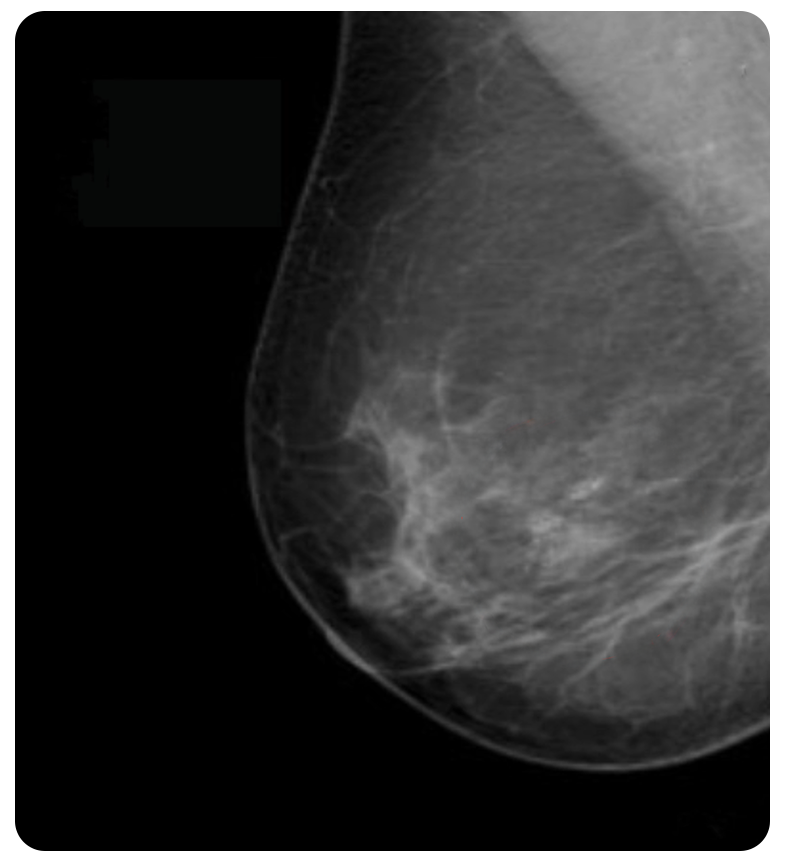

Comparison between the image of the same breast

Traditional Mammography

Revolutionary Cone Beam Breast CT